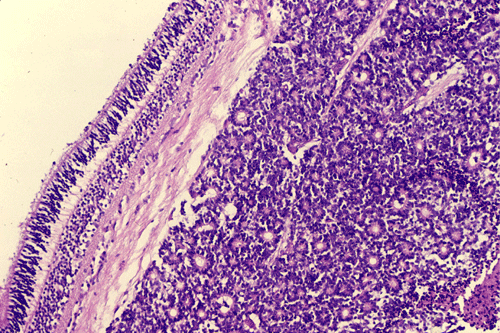

On the whole mount of the globe, there is an exophytic neoplasm that occupies about one-third the volume of the vitreous. The surface of the retina is free of tumor deposition (Panel A). The retina is detached by the mass. There are some pink, necrotic material at the core of the tumor (Panel B). On medium and high-magnification, the tumor is composed of densely packed small cells with hyperchromatic nuclei  without prominent nucleoli. A large number of the cells arrange in rossettes with a well-defined luminal border (Flexner-Wintersteiner rossettes) (Panel C and D). The tumor is confined within the globe and the optic nerve is free from invasion.

The pathology is typical for that of a small blue cell tumor with morphologic and immunohistochemical features comparable to medulloblastoma, supratentorial primitive neuroectodermal tumors, and adrenal neuroblastomas. Tumor cells have small to medium sized, hyperchromatic nuclei with clumpy chromatin and without prominent nucleoli. Only a small to minute amount of cytoplasm is present.  Mitotic figures are numerous. Retinoblastoma has a striking tendency to undergo necrosis. The tumor cells that are closer to the blood vessels are more likely to remain viable. Calcifications are common findings in the necrosis.  Some of the nucleic acid liberated from these necrotic cells becomes absorbed in the walls of blood vessels giving them a deep blue appearance.

Most often, tumor cells arrange in Flexner-Wintersteiner rosettes typified by tall cuboidal cells formaing a small, circumstribed lumen with well defined limiting membrane on the luminal side. The tumor nuclei are found at the basal end of the cuboidal cells while the apical end contains the cytoplasm. Small projections are protruding from the luminal surface into the lumen and these projections represent residual features of photoreceptor cells. Homer-Wright rosettes can also be found but are less common. In between the rosettes are solid sheets of poorly differentiated tumor cells.